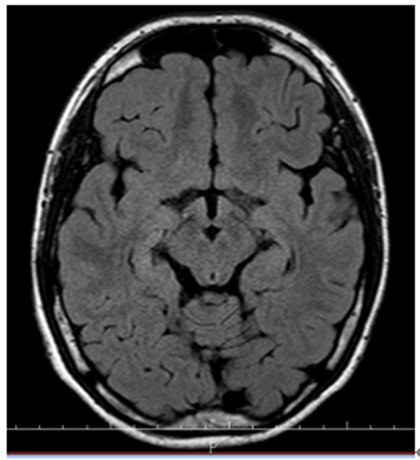

入院查体:皮肤细腻,声音尖细,乳房发育,阴茎短小。神清,十二对颅神经检查均未见异常,全身深浅感觉及复合感觉未见异常,肌营养、肌张力、肌力未见异常,共济运动未见明显异常,未见明显不自主运动,生理反射存在,病理反射未引出。辅助检查:我院头颅MR:1.右侧颞枕顶叶局部皮层稍增厚,请结合临床;2.右侧海马硬化待排;3.脑白质少许脱髓鞘灶;4.双侧上颌窦、筛窦及额窦炎症。VEEG:间期:癫痫样放电,右半球,右前头部。

入院诊断:癫痫。入院后完善相关检查,VEEG:发作期:眨眼→左侧面肌、上肢强直→左侧偏转→BAST(左)→GTCS。MRI:右侧眶额回灰白质分界不清,弥漫性脑萎缩。PET:右侧额极及内侧面低代谢,右侧眶额回稍低代谢,右侧岛叶代谢减低。韦氏智力:全量表83,言语78,操作91;记忆63。染色体结果:47,XXY。

▲1 T2FLAIR轴位右侧框额回灰白质分界不清